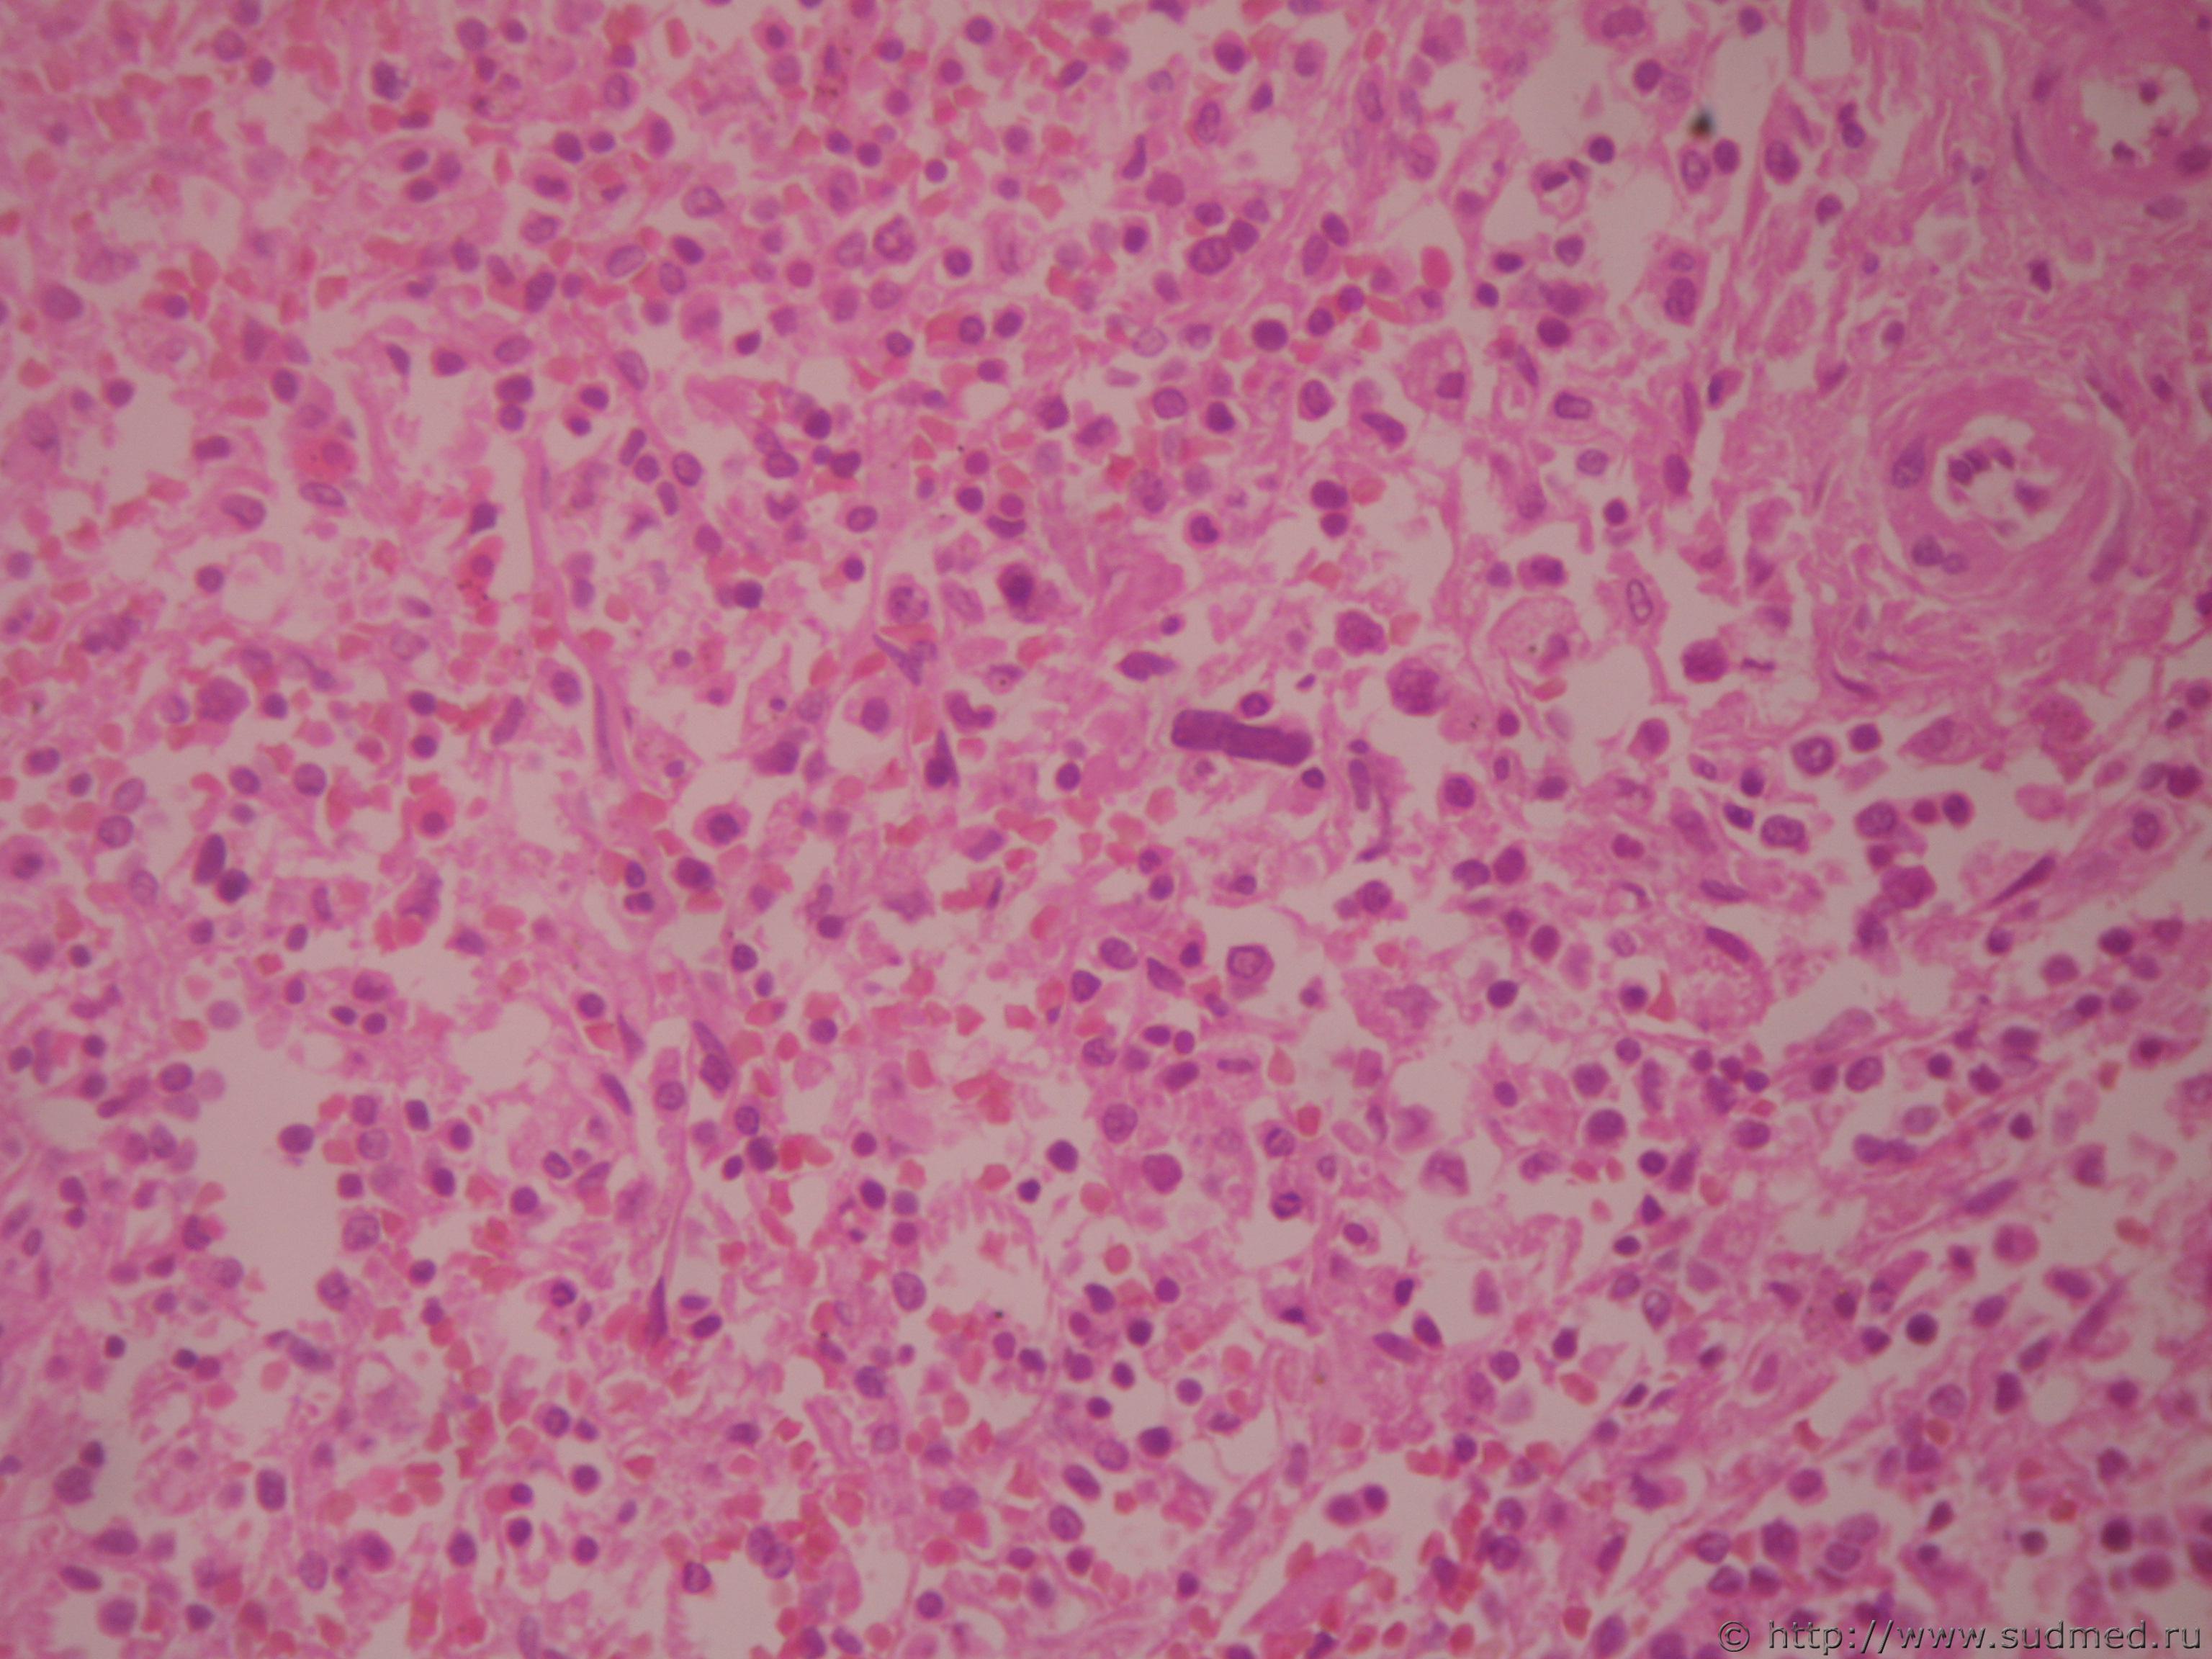

мекариоциты при шоке

[quote name='чеснок' post='159075' date='19.11.2012 - 14:28']мне известно (не помню откуда), что при шоке в капиллярах стенок альвеол выявляются мегакариоциты, а в других органах они могут быть?